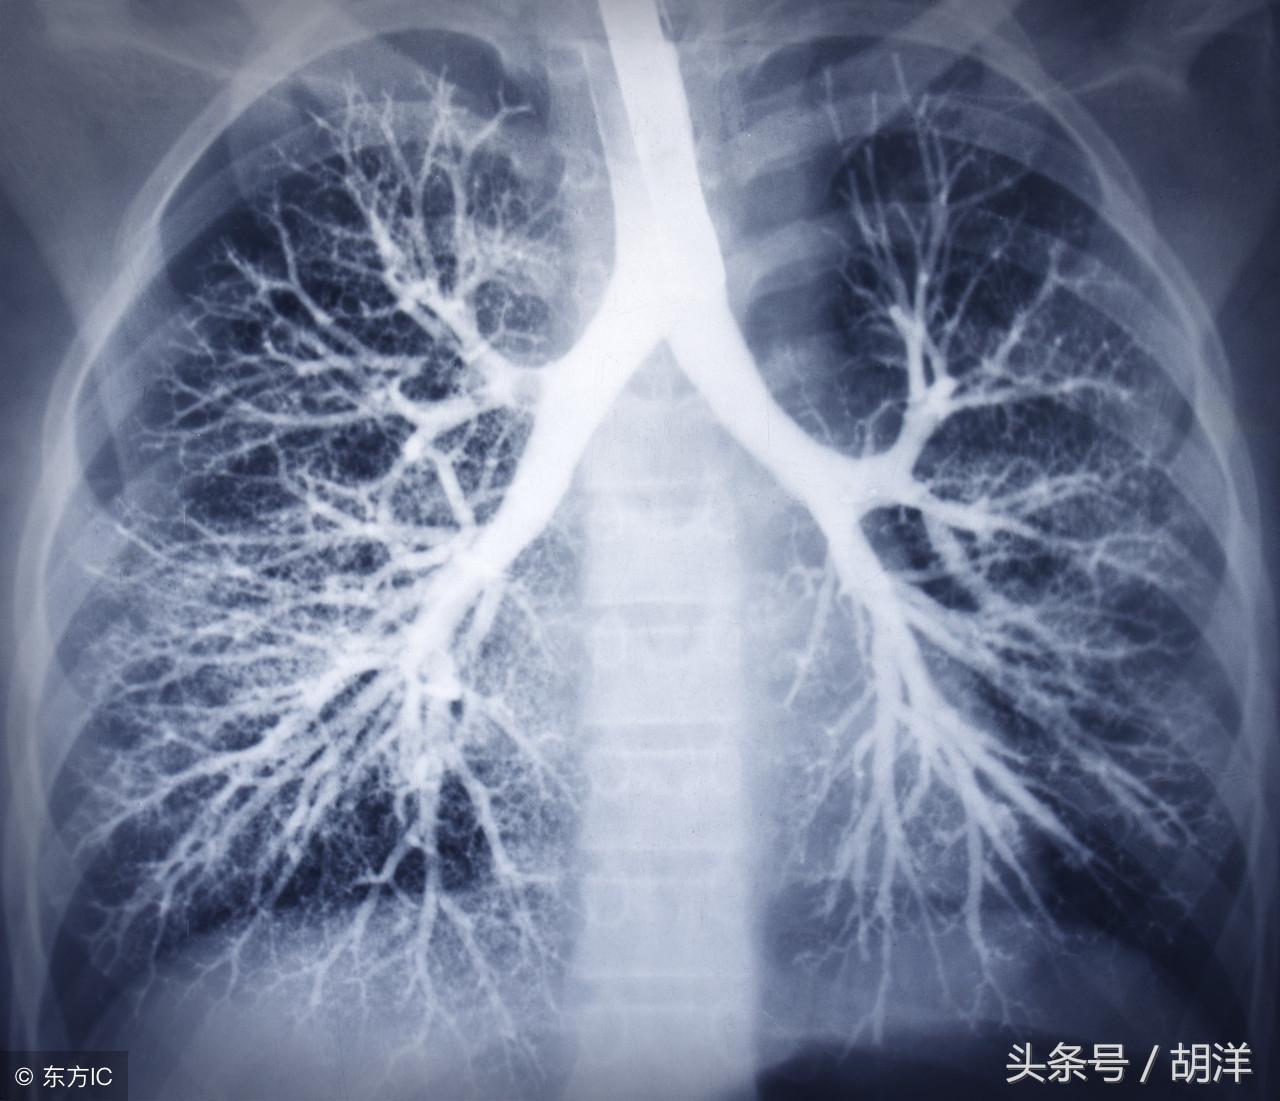

咳血又称咯血,是呼吸科一个比较严重的症状,由于其可能提示肺部肿瘤等严重疾病而受到重视,但事实上在引起咯血的病因中,肺部恶性肿瘤所占的比例并不是很大,但很多人因咯血而焦虑异常,特别是咯血久治不愈情况下,更加令人无法正常的生活和学习,那么哪些疾病可能导致反复发作痰中带血或者咳出满口鲜血呢?

支气管扩张是一种支气管管壁结构破坏性疾病,正常情况下,支气管是一个带有弹性,拥有一定管径的能够维持正常呼吸通气的结构,当管壁结构受到破坏时,气管会受到被动的牵拉而扩张,管壁的血管由于弹性较小,容易被撕扯呈血管瘤改变,一旦胸腔内血流压力增大可能冲破血管瘤变薄的管壁而导致大咯血,少量渗血时则呈现为痰中带血。

肺结核是一种肺部传染性疾病,是由于结核菌在肺部生长并破坏肺部结构导致的,对于肺部的损害很大,寄生的肺组织局部甚至会完全毁损形成干酪样坏死物排出体外,这样的破坏难免侵蚀血管导致出血,也是大咯血的原因之一。

肺癌也是较为常见的导致咯血的原因,恶性肿瘤细胞对于肺组织的侵蚀是其他疾病无法比拟的,几乎可以侵犯肺部正常组织中的所有结构,包括血管,另外,肺癌癌肿由于生长过快,其表面的细胞可能会因为得不到充足的血液供应而坏死,这样的坏死很容易产生渗血,是引起痰中带血的常见原因。

肺炎引起咯血的原因和肺结核类似,都是由于肺部细菌感染后破坏正常肺结构引起渗血以及血管破裂所致。

曲霉菌是一种常见的真菌,正常情况下,曲菌很少感染肺部结构正常,免疫力良好的人群,当肺部受到破坏,特别是形成较大空洞和支气管扩张时,曲霉菌可以趁机进入空洞扩张的支气管内与其中渗出的白细胞、纤维素等成分形成球状结构,成为曲菌球,曲菌球在空洞内能够自由的活动,对空洞壁有机械性的损伤,当损伤到管壁变异的血管瘤时,极有可能导致大出血。